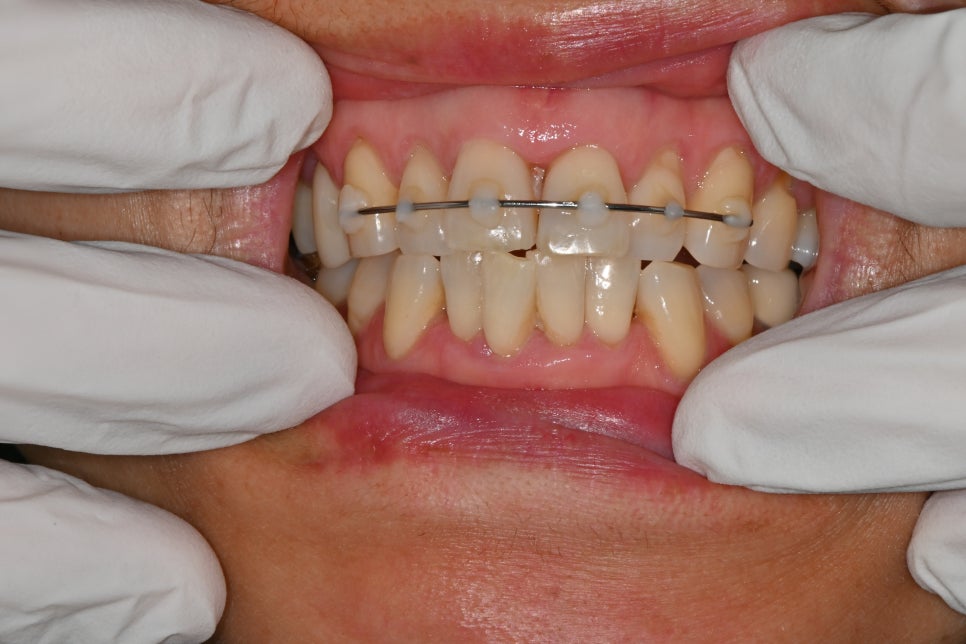

치조골 골절 및 앞니 고정장치

- 치조골 골절 & 앞니 고정술

충격으로 앞니가 뒤로 밀리거나 흔들리면,

반드시 제 위치로 되돌리고 일정 기간 고정해야 합니다.

이번 케이스에서도

앞니 부목 지지대 고정 시술

이 이루어졌습니다.

이는 치아가 다시 안정적으로 뼈와 붙도록 돕는 과정입니다.

고정을 하지 않거나 늦어지면, 치아가 점점 더 움직이거나 신경이 괴사될 위험이 높습니다.